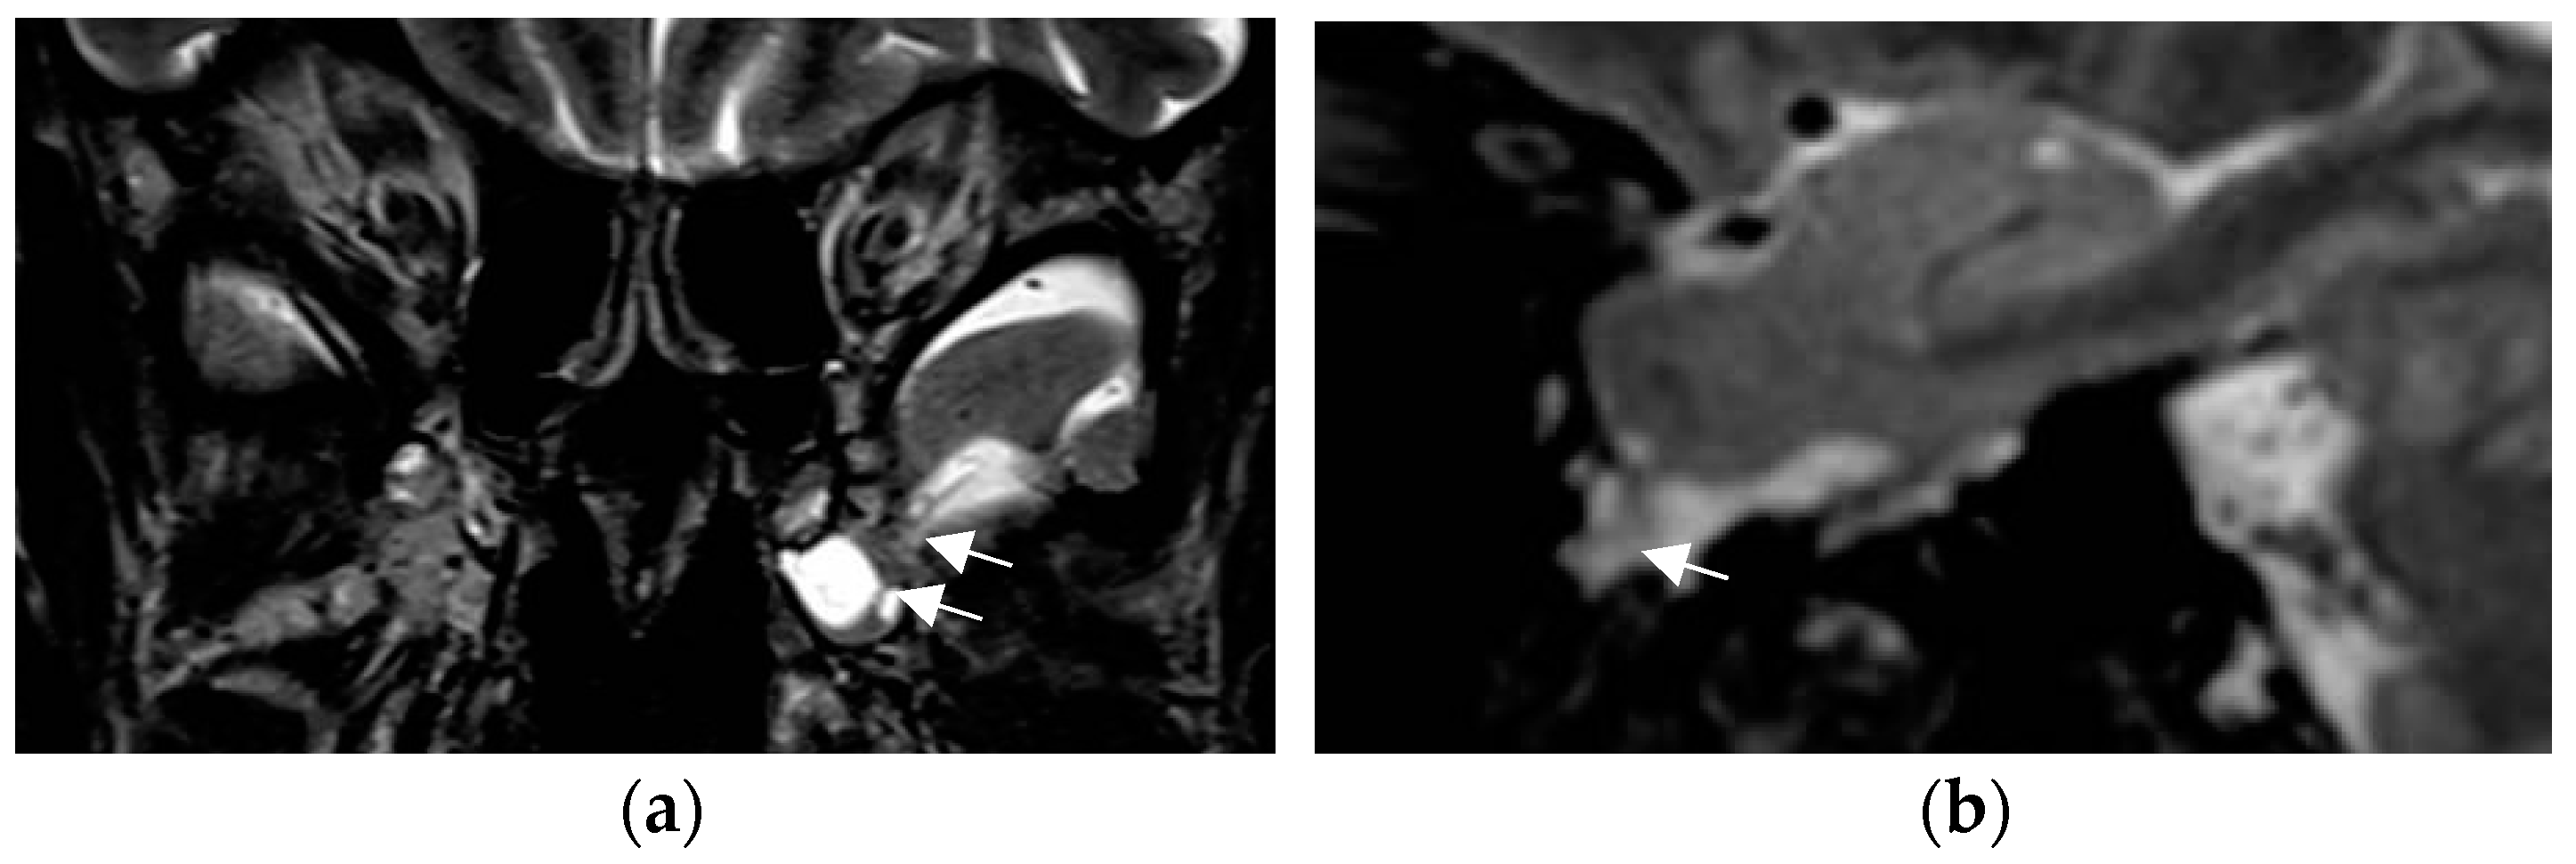

The SWI sequence depicts hemosiderin and calcification and thus renders visible cavernoma and cerebral and superficial siderosis as figureheads of cerebral amyloid angiopathy or posttraumatic or postsurgical siderosis (Figure 4).

Figure 4.

Amyloid angiopathy as evidenced by superficial siderosis within the right central sulcus on SWI sequence (arrow in (a)); invisible on the corresponding axial T2 w image (b); patient with focal seizures localized within the left hand.

Based on the SWI sequence, additional information was obtained in 13/59 (22%) of patients assessed by 1.5T MR [73].

A less-recognized feature of the SWI sequence is the paramagnetic effect of deoxyhemoglobin as a surrogate marker of vessel caliber. Pseudonarrowing of vessels may serve as a sign of regional hyperperfusion (Figure 5) and, thus, may indicate nonconvulsive status epilepticus [74,75].

Figure 5.

Non-convulsive absence status with left-sided pseudonarrowing of the mesiotemporal portion of basal vein (arrow in (a)) and hippocampal veins (arrowhead in (a)) as compared to the normal right side and mesiotemporal hyperperfusion; (CBF = cerebral blood flow image (b)) indicated by left light-green mesiotemporal hypervascularity (arrow in (b)).